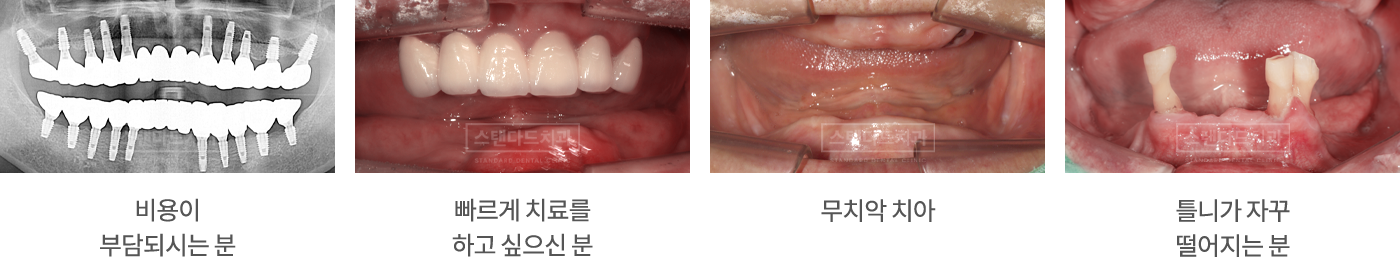

풀아치 임플란트가 필요하신 분

임플란트 6개 식립으로 전체 치아 기능 회복

식립 갯수와 비용은 낮추고 Down!

치료기간은 줄고 Speed!

떨어지는 틀니는 이제그만 Stop!